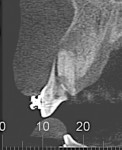

When the patient was 18 years old, root fracture of tooth No. 8 occurred, which was an indication for extraction (Figure 1 and Figure 2). Six months later, tooth No. 9 was also designated for extraction due to recurrent periapical lesions (Figure 4 and Figure 5). The following treatment plan was established: extraction of teeth Nos. 8 and 9 and performance of IDR at two different times (Figure 3 through Figure 11); placement of two ceramic abutments and all-ceramic crowns (Figure 12 through Figure 15); and continued orthodontic treatment to finalize the case.

The same procedure was used for tooth No. 9. Six months after the second procedure, definitive restorations fabricated from zirconia-ceramic were placed for both central incisors. The patient was clinically and radiographically followed every 6 months. Figure 12 through Figure 15 show the occlusal and buccal clinical aspect at 3 years follow-up, and Figure 16 and Figure 17 show the tomographic follow-up of the buccal plate bone.